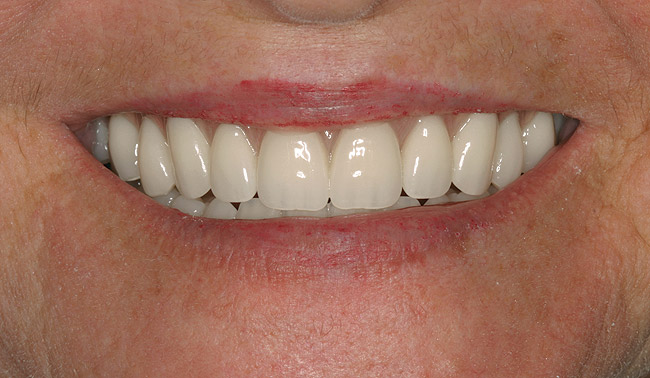

In overdenture therapy, prosthetic design can be divided into two groups: stress-broken and rigid. Stress-broken prostheses require fewer implants, with attention to biomechanical design features to allow for rotation (stress-breaking) of the prostheses around the implant locations. These prostheses are essentially tissue-supported and implant-retained. They replace the adhesive/glue, providing needed retention, comfort, and support. An example would include two implants in site Nos. 23 and 26, with either solitary anchor systems (ball or stud attachments) or a splinted bar-overdenture design (Figure 9 through Figure 11). Masticatory function is improved and patient satisfaction increased. Rigid prostheses require multiple implants, with the forces being transferred from the supra-infrastructure directly to the implants. These prostheses are implant-supported and implant-retained. The design can be removable or fixed (Figure 12 through Figure 16), depending on patient- and operator-mediated preferences.24-27 Within the fixed group of prostheses, materials used may vary from acrylic-fused-to-metal, porcelain-fused-to-metal, or all-ceramic. The cost of these material choices varies significantly, with acrylic options providing the most affordable, entry-level approach for the patient.14